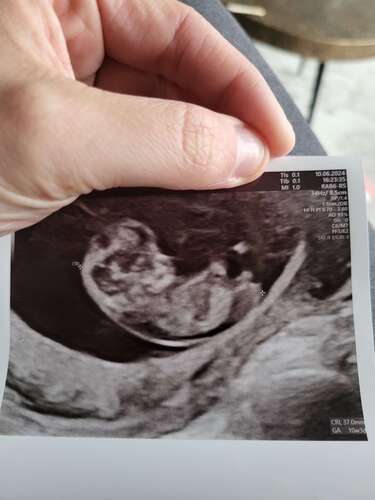

Net de termijnecho gehad en mijn uitgerekende datum is ook 2 januari 馃グ zo leuk om dit weer mee te mogen maken, dat je al zo goed alles kunt zien.